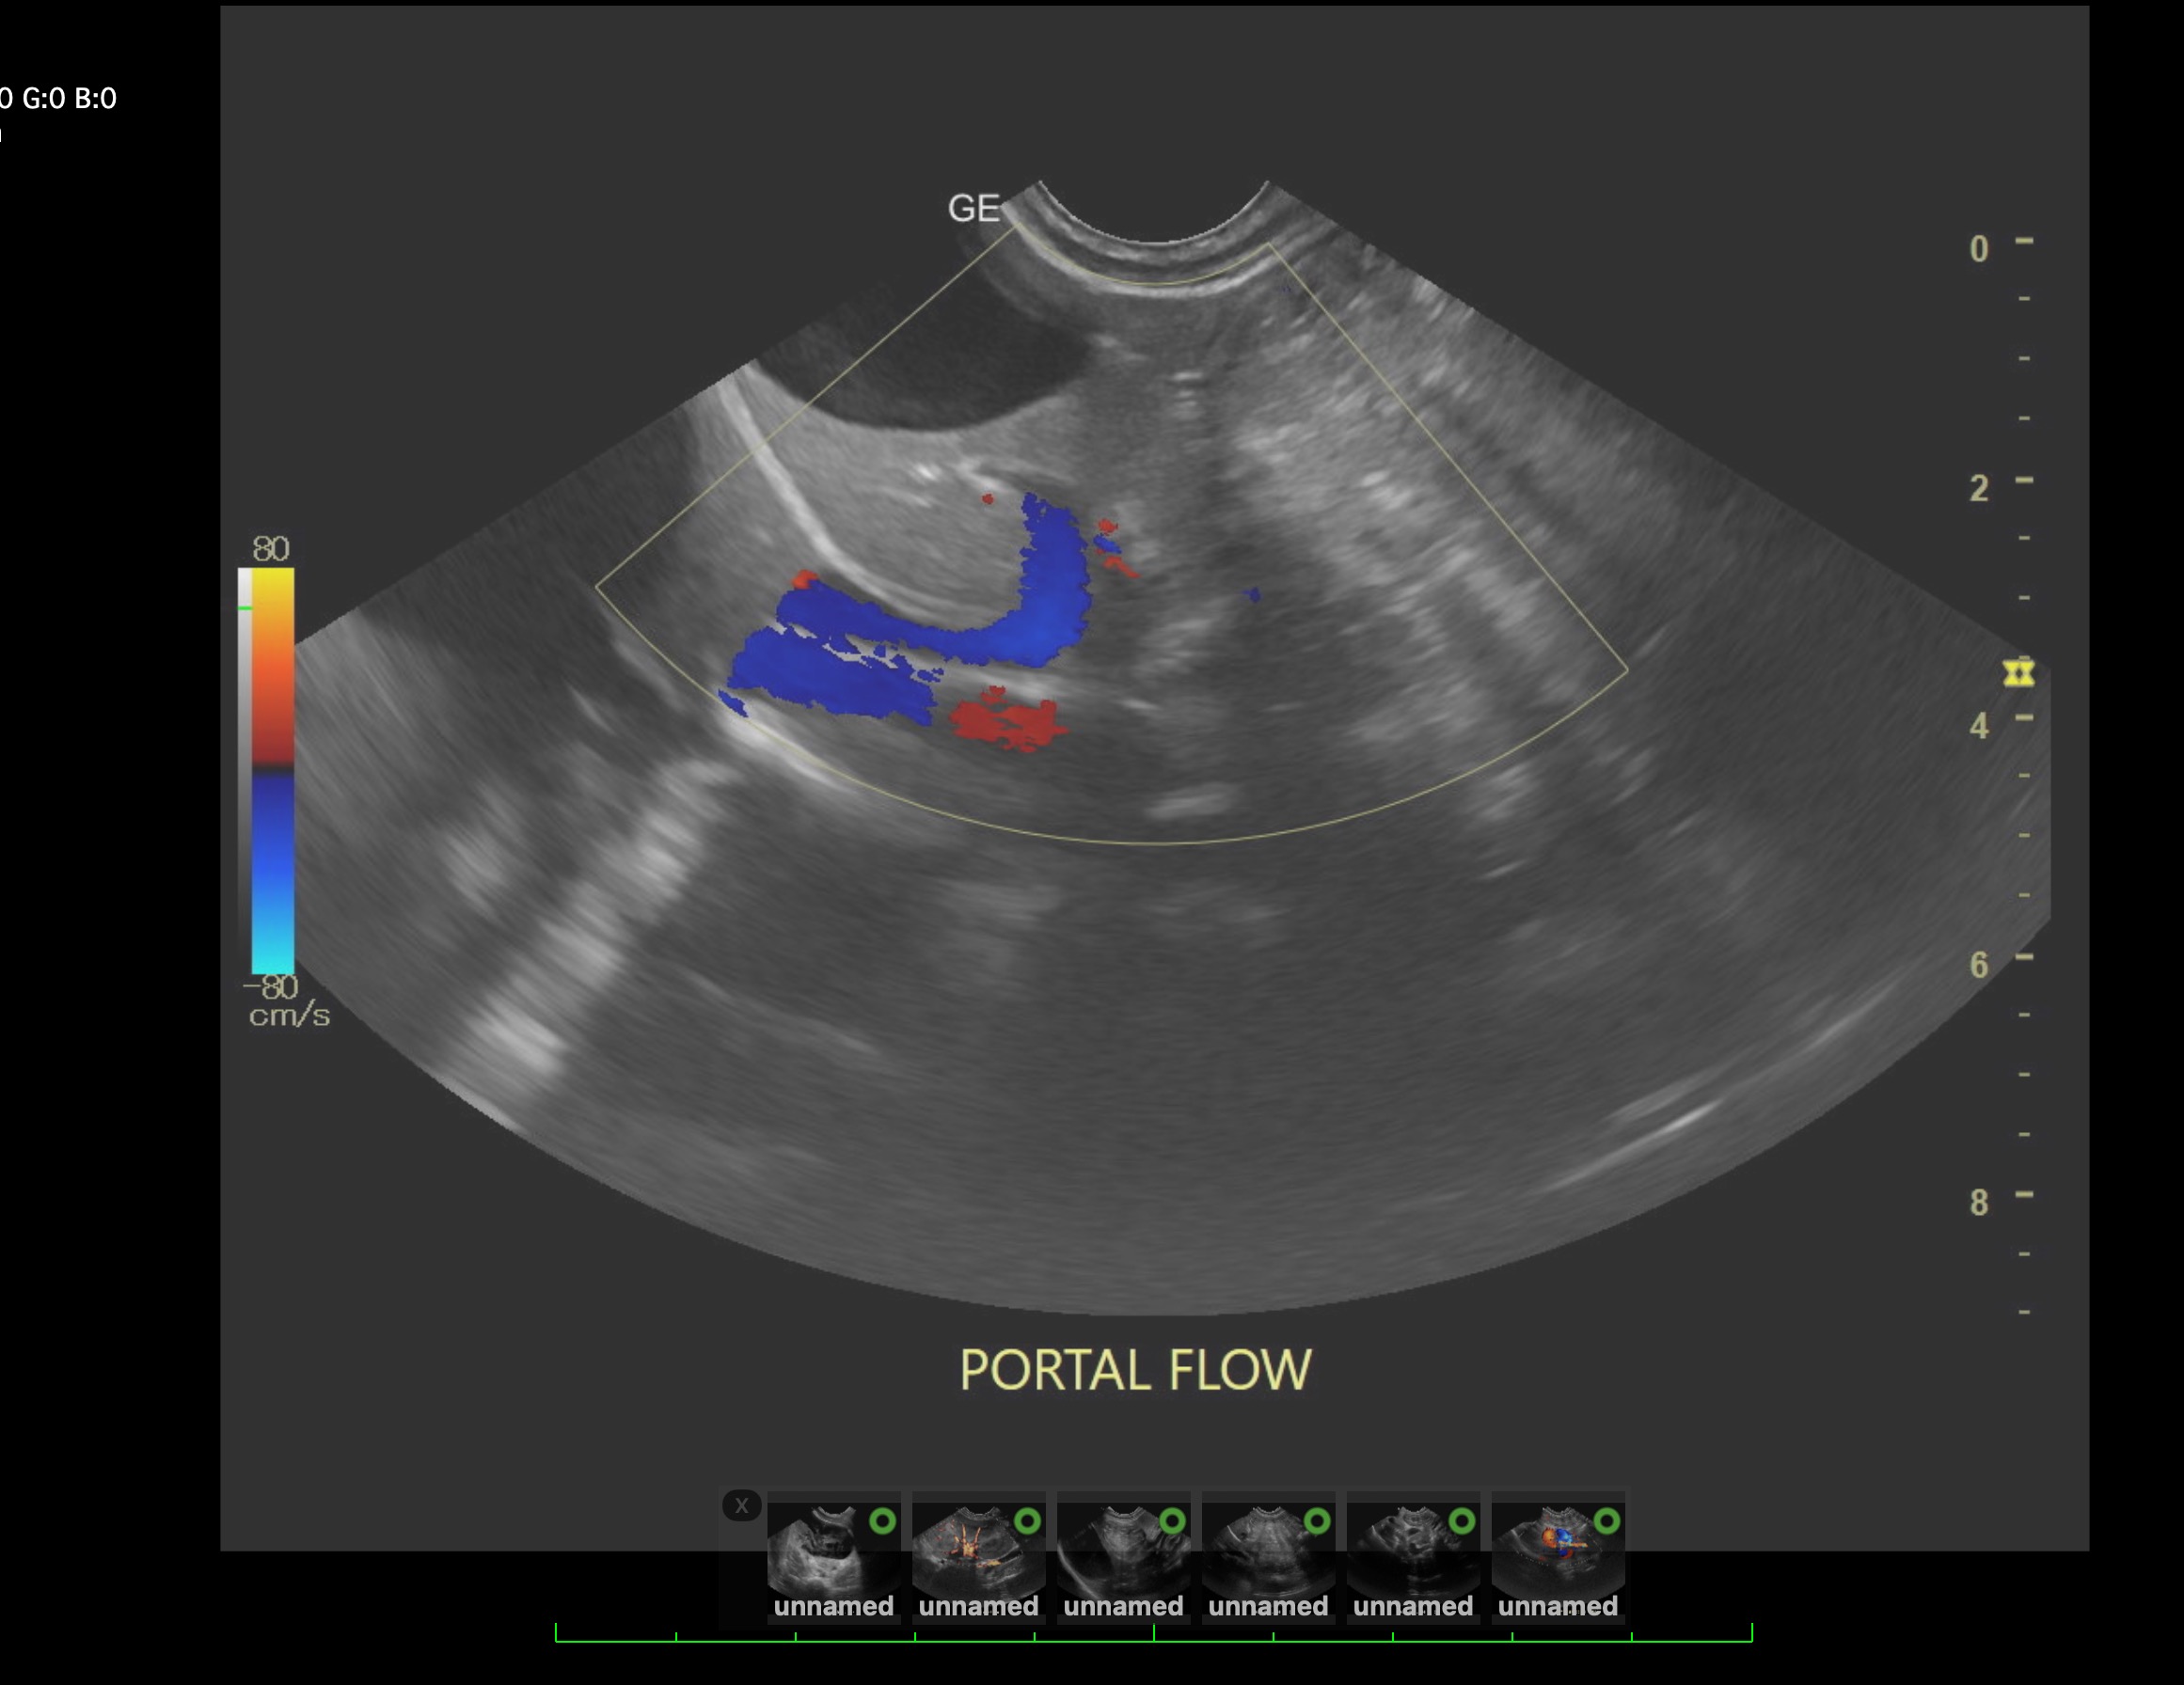

Labwork (fasted): TP 4.5, Alb 2.5, ALP 144, ALT 155, GGT 3, Bili 0.4, Cre 0.3, Cho 51, Amy 266 CBC – HCT 39%, Hgb 12.0 UA – USG 1.030pH 6, 1+ bilirubin, WBC 4-10/hpf, rods 26-50/hpf Negative Accuplex Bile Acids: Pre 299.2, Post-meal – 90.7